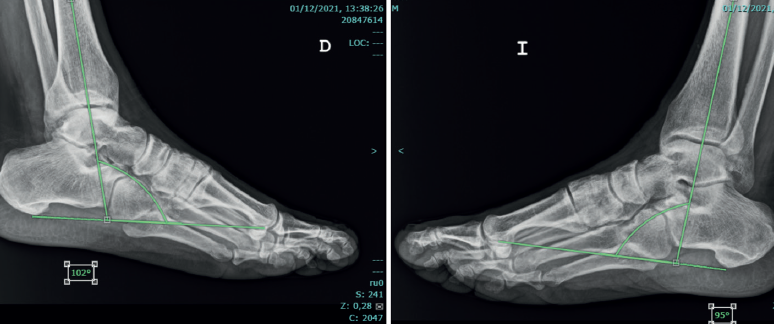

Al año de la rotura del TA, se analizaron las variables demográficas, la escala Achilles Tendon Total Rupture Score (ATRS)(14), la de la American Orthopaedic Foot and Ankle Society (AOFAS)(15), la capacidad de realizar puntillas bi- y monopodales y permanecer en dicha posición durante 3 segundos (Figura 1). Asimismo, se analizó la pérdida del equino fisiológico mediante evaluación clínica con un goniómetro (grados del equino con el paciente en decúbito prono) y se comparó con la extremidad sana (Figura 2). Para evitar sesgos del investigador, se correlacionó esta medida clínica con goniómetro con un estudio radiológico: se realizaron radiografías de ambos tobillos comparativas en posición de decúbito prono con la extremidad en descarga y la rodilla extendida, y se midieron los grados digitalmente con el sistema informático.

La media de la diferencia de equino residual clínico respecto el lado sano era de 6,1 ± 4,2° (más plantígrado el lado afecto). Esta medida se correlacionó con la diferencia de equino residual medida radiológicamente, siendo de 5,8 ± 4,5°.